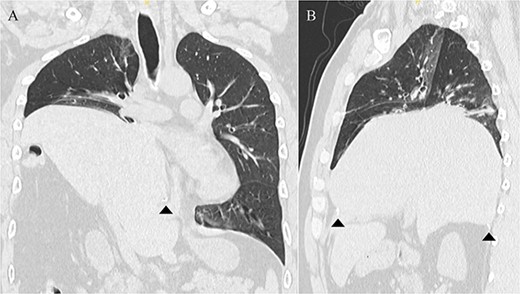

A 41-year-old man was referred to our hospital because of chest pain. Chest computed tomography (CT) revealed an anterior mediastinal tumor, and it was resected by median sternotomy. Pathological diagnosis was thymic cyst. Postoperatively, the patient developed right phrenic nerve palsy due to intraoperative stretch of the nerve and dyspnea on effort. After a year, the phrenic nerve palsy didn’t improve. He then underwent diaphragmatic plication by a right mini-thoracotomy. The elevated diaphragm was resected using an endostapler (Powered Echelon Flex®, black and green cartridges) without any reinforcement. After the second surgery, the surgical stump left by the endostapler ruptured, resulting in diaphragmatic rupture and defect. Chest CT revealed a large diaphragmatic defect (arrowhead) and prolapse of the liver into the thoracic cavity (Fig. 1). However, this condition had been misdiagnosed as the recurrence of diaphragmatic elevation for a year. His dyspnea increased in the supine position, and pulmonary function testing revealed restrictive ventilatory impairment, which led the correct diagnosis of diaphragmatic rupture. The vital capacity (VC) and %VC were 1.86 L and 39.8%, respectively. A year after the second surgery, we then repaired the diaphragmatic defect by right thoracotomy. The surgical view of the thoracic cavity showed that the liver had prolapsed from the large diaphragmatic defect, which measured 15 cm (Fig. 2). Severe adhesion was present between the liver and the edge of the torn diaphragm including the torn staple line and was carefully dissected. The diaphragmatic defect was closed with a 1 mm thick PTFE patch. Moreover, the diaphragm was reconstructed using a second 1 mm thick PTFE patch above the original placement, overlaying the diaphragmatic defect that had been closed by the first PTFE patch (Fig. 3, arrow). The second PTFE patch was fixed to the lower ribs by non-absorbable suture (Fig. 3, arrowhead). The operating time was 325 min, and the blood loss volume was 50 mL. The postoperative course was favorable, and the patient was discharged 7 days after surgery. Three months after the third surgery, his symptoms improved, and pulmonary function testing revealed that the VC and %VC were 2.24 L and 48.1%, respectively. Postoperative chest computed tomography revealed PTFE patch maintained a good position (Fig. 3).

Chest computed tomography showing that the liver had prolapsed into the thoracic cavity. (A) Coronal view. (B) Sagittal view. The arrowhead indicates the edge of the torn diaphragm, including the torn staple line.